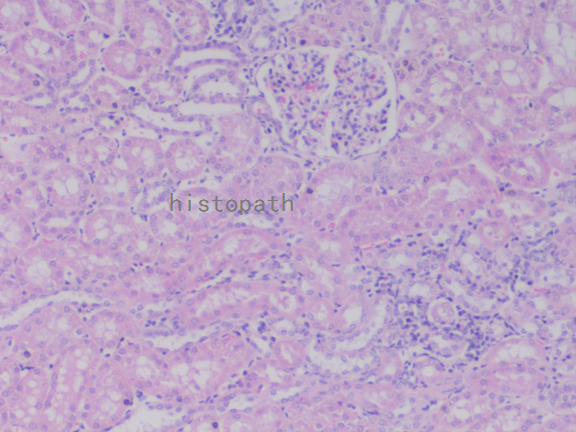

苏木精--伊红染色法(hematoxylin-eosin staining),简称HE染色法,石蜡切片技术里常用的染色法之一。苏木精染液为碱性,主要使细胞核内的染色质与胞质内的核酸着紫蓝色;伊红为酸性染料,主要使细胞质和细胞外基质中的成分着红色。HE染色法使组织学、胚胎学、病理学教学与科研中最基本、使用最广泛的技术方法。

染色结果:

细胞核呈蓝色,细胞质、肌肉、结缔组织、红细胞、嗜曙红颗粒呈不同程度的粉红色。钙盐、软骨基质和各种微生物也可染成蓝色或紫蓝色。核仁呈红色。着色情况不仅与组织或细胞的种类有关,也随其生活周期及病理变化而改变。质量优良的HE染色切片样本,细胞核与细胞质蓝红对比明显,胞核鲜明,核膜及核染色质颗粒均清晰可见。